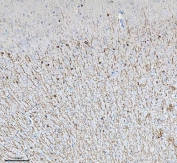

IHC staining of FFPE rat brain tissue with CNP antibody. HIER: boil tissue sections in pH8 EDTA for 20 min and allow to cool before testing.

IHC staining of FFPE mouse brain tissue with CNP antibody. HIER: boil tissue sections in pH8 EDTA for 20 min and allow to cool before testing.